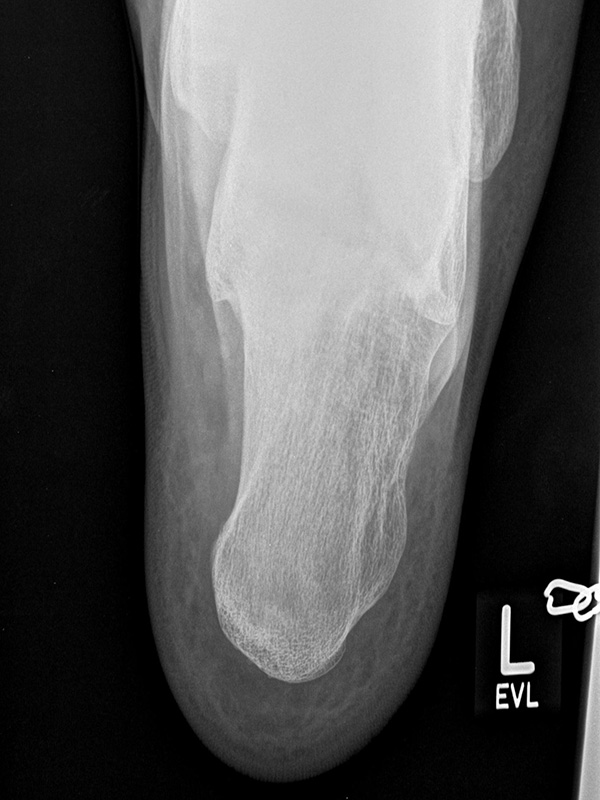

Fersenbein in 2 Ebenen

Indikation:

• Fersenbeinfrakturen.

• Entwicklungsstörungen bei Kindern (z.B. Apophysitis calcanei).

• Verlauf nach knöchernen Korrekturen.

• Haglund-Exostose.

• Traktionssporn.

• Plantare fasciitis.

Fersenbein axial

Positionierung:

• Patient in Rückenlage.

• Fuß in extremer Dorsalflexion. Unterstützung der Dorsalextension mit einer Mullbinde.

• Filmposition horizontal am Boden.

• Röntgenröhre um 45° caudocranial gekippt.

• Zentralstrahl auf die Mitte des Fersenbeins fokussiert.

Kennzeichen des Röntgenbildes:

• Calcaneus darf nicht verkürzt erscheinen.

• Der Zentralstrahl soll senkrecht auf das Fersenbein treffen, damit es nicht zu Verzerrungen kommt.

Besondere Bemerkungen zum Beispielbild:

• Unauffällige Darstellung des Fersenbeins.

Zur Vollansicht und zum Lesen der Bildbeschreibung bitte die Bilder anklicken.

Fersenbein lateral

• Patient in Seitenlage.

• Fuß mit der Außenseite aufliegend.

• Ferse liegt parallel zum Tisch.

• Röntgenröhre 90° zur Senkrechten.

• Zentralstrahl von lateral nach medial, zentriert auf das Fersenbein ca. 1-2 Querfinger distal der Malleolen.

• Seitliche Darstellung des Fersenbeins mit scharfen Knochenkonturen.

• Gut einsehbares unteres Sprunggelenk (Articulatio talocalcaneonaviculare).

• Gut einsehbares Gelenk zwischen Calcaneus und Os cuboideum.

• Darstellung der Kalkaneus seitlich.

• Kleiner Traktionssporn im Insertionsbereich der Achillessehne.

• Großes Os trigonum dorsal des Talus.